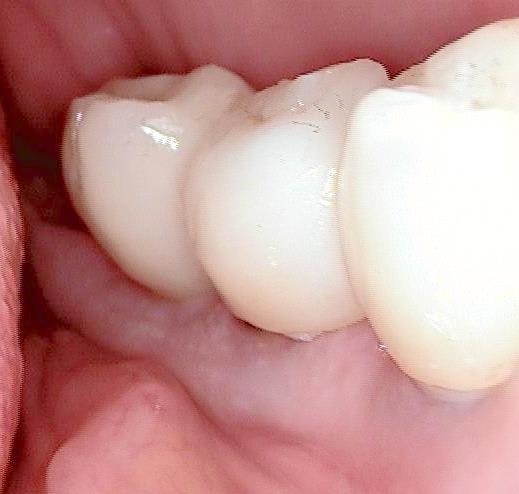

non, c'est pas de l'occlusion dont je parle...mais de l'adaptation prothèse/pilier implantaire (il y a un espace entre l'implant et l'armature métallique de la prothèse au niveau des molaires...mais pas que...) source de rétention de plaque dentaire et donc risque potentiel de périimplantite à ce niveau...

ah je comprends mieux!!! :-),les "espaces" que tu vois ce sont des prep caps en zircon avec prothèse zircone il n y donc pas d accumuation de plaques sinon tu aurai raison ! (bonne remarque). La couronne ne touche pas" l assiette" (en allemand on parle d assiette...)du prep cap ...

tu as raison ca serait idéal mais

-il n y a pas d accumulation de plaque quand on n utilise du zircon

-les "espaces" sont sugingivales

-les prep caps sont des couronnes en zircon pré fabriquées et ce n est pas nécessaire d avoir les extrémites des couronnes jusqu à la base des prep caps , meme si les couronnes sont dans une position termine-tangentiale

-la base des prep caps dans ce cas là sont environ 4/5mm subgingival, donc après avoir cémenté les bridges on ne pourrait pas nettoyer le cement si la couronne allait jusqu´à la base des prep caps.

-Enfin ici il s ´agit de plusieurs implantations immédiates durant lesquelles j utilise toujours les prep caps.